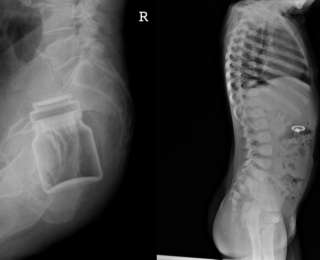

Воздух позволяет увидеть бутылку в прямой кишке (тёмная область)

Баночка дезодоранта

Вот так выглядит кардиостимулятор. Хоть он на своём месте )